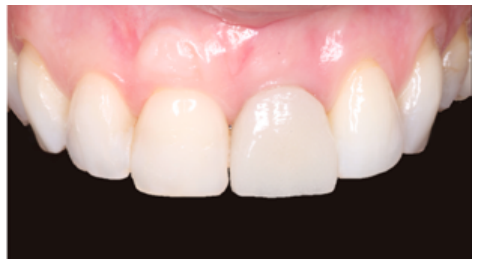

Clinical case: A 32-year-old female patient who attended for a possible root fracture of the upper left central incisor (ULCI), accompanied by a periodontal abscess at the bottom of the vestibule of the same tooth. A clinical and radiological examination established that the prognosis of the ULCI was unfavourable for conservative treatment. After evaluating the clinical features of the case, the treatment plan to extract the ULCI followed immediately by an osseointegrated implant (OII) and loading of a provisional prosthesis on the implant.

Conclusions: Rehabilitation on implants in situations of tooth loss in the aesthetic anterior sector, especially in young patients, requires a multidisciplinary treatment plan to extract the tooth and insert an OII in the correct 3-dimensional position. Various aspects need to be taken into account for this, particularly the residual remaining bone, the position of the gingival margin and preservation and conditioning of the peri-implant hard and soft tissues by means of grafts and proper handling of provisional prosthesis, until an ideal emergence profile and gingival contour is achieved before the final crown.

The benefits of immediate loading include a marked reduction in surgical interventions, less temporary dilation of the treatment and even better psychological and social wellbeing for the patient. In cases with a significant aesthetic requirement, immediate loading or provisionalisation, and post-extraction placement of the OII minimise alterations due to tooth loss and maintain the emergence profile, soft tissue contour and gingival papillae5-7.

Different protocols have also been established for the management of the anterosuperior aesthetic sector, in addition to performing the immediate implant and provisional crown, including placing material between the OII and the buccal cortical to minimise possible collapse and the management of peri-implant soft tissue8-11.